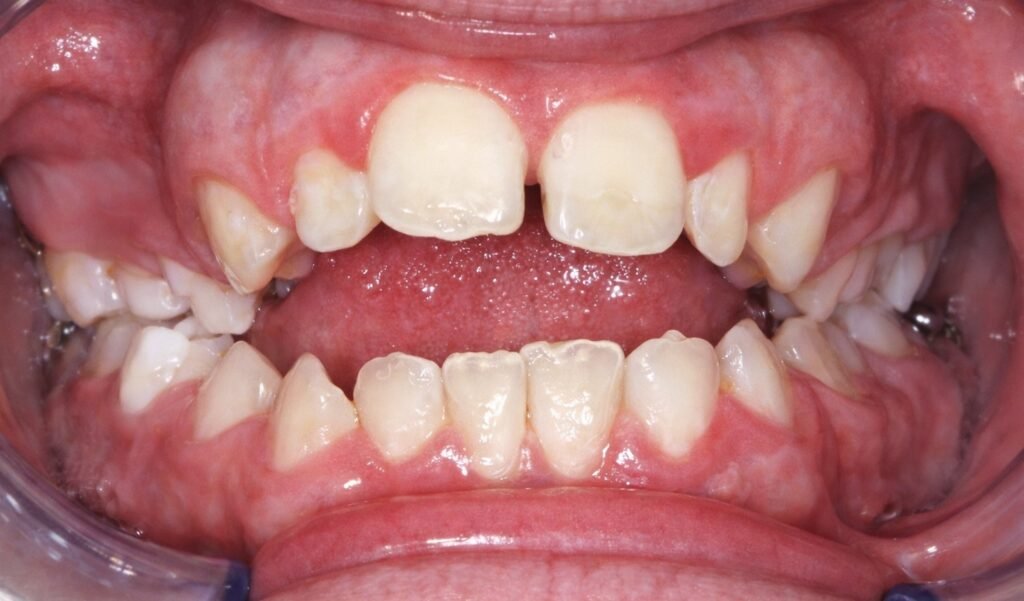

La dysharmonie dento-maxillaire (DDM) correspond à une disproportion entre les dimensions mésio-distales des dents permanentes et le périmètre des arcades alvéolaires correspondantes. En termes plus simples, il existe un déséquilibre entre la taille des dents et l’espace disponible pour les accueillir sur l’arcade dentaire.

Cette disproportion rompt la continuité normale des arcades dentaires au niveau des faces proximales. Le signe clinique le plus évident est un encombrement des arcades dentaires, visible dès l’examen initial du patient.

DDM par excès : Les dents sont trop volumineuses par rapport à l’arcade, ou l’arcade est trop petite pour accueillir des dents de taille normale. C’est la forme la plus courante, responsable de l’encombrement dentaire.

Concerne les incisives et canines. C’est la forme la plus visible esthétiquement et souvent celle qui motive la consultation. L’encombrement incisif se manifeste par des chevauchements, des rotations ou des malpositions des dents antérieures.

Atteinte purement dentaire : Conséquence directe de l’encombrement avec malpositions incisives, canines en ectopie, rotations, linguo-occlusions localisées, sans retentissement sur le profil facial cutané.

- Encombrement incisif patent

- Dénudation accentuée d’une incisive avec parfois absence de gencive attachée

- Facettes d’abrasion sur les dents en occlusion inversée

- Mobilité d’une dent inférieure en vestibulo-occlusion